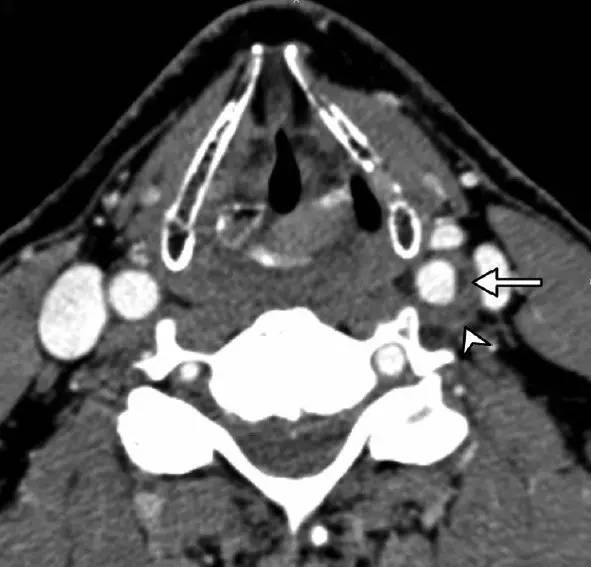

例2:CTA显示左侧颈内动脉周围后外侧偏心血管周围浸润(短箭头),以及明显低密度为内膜软斑块(长箭头)。